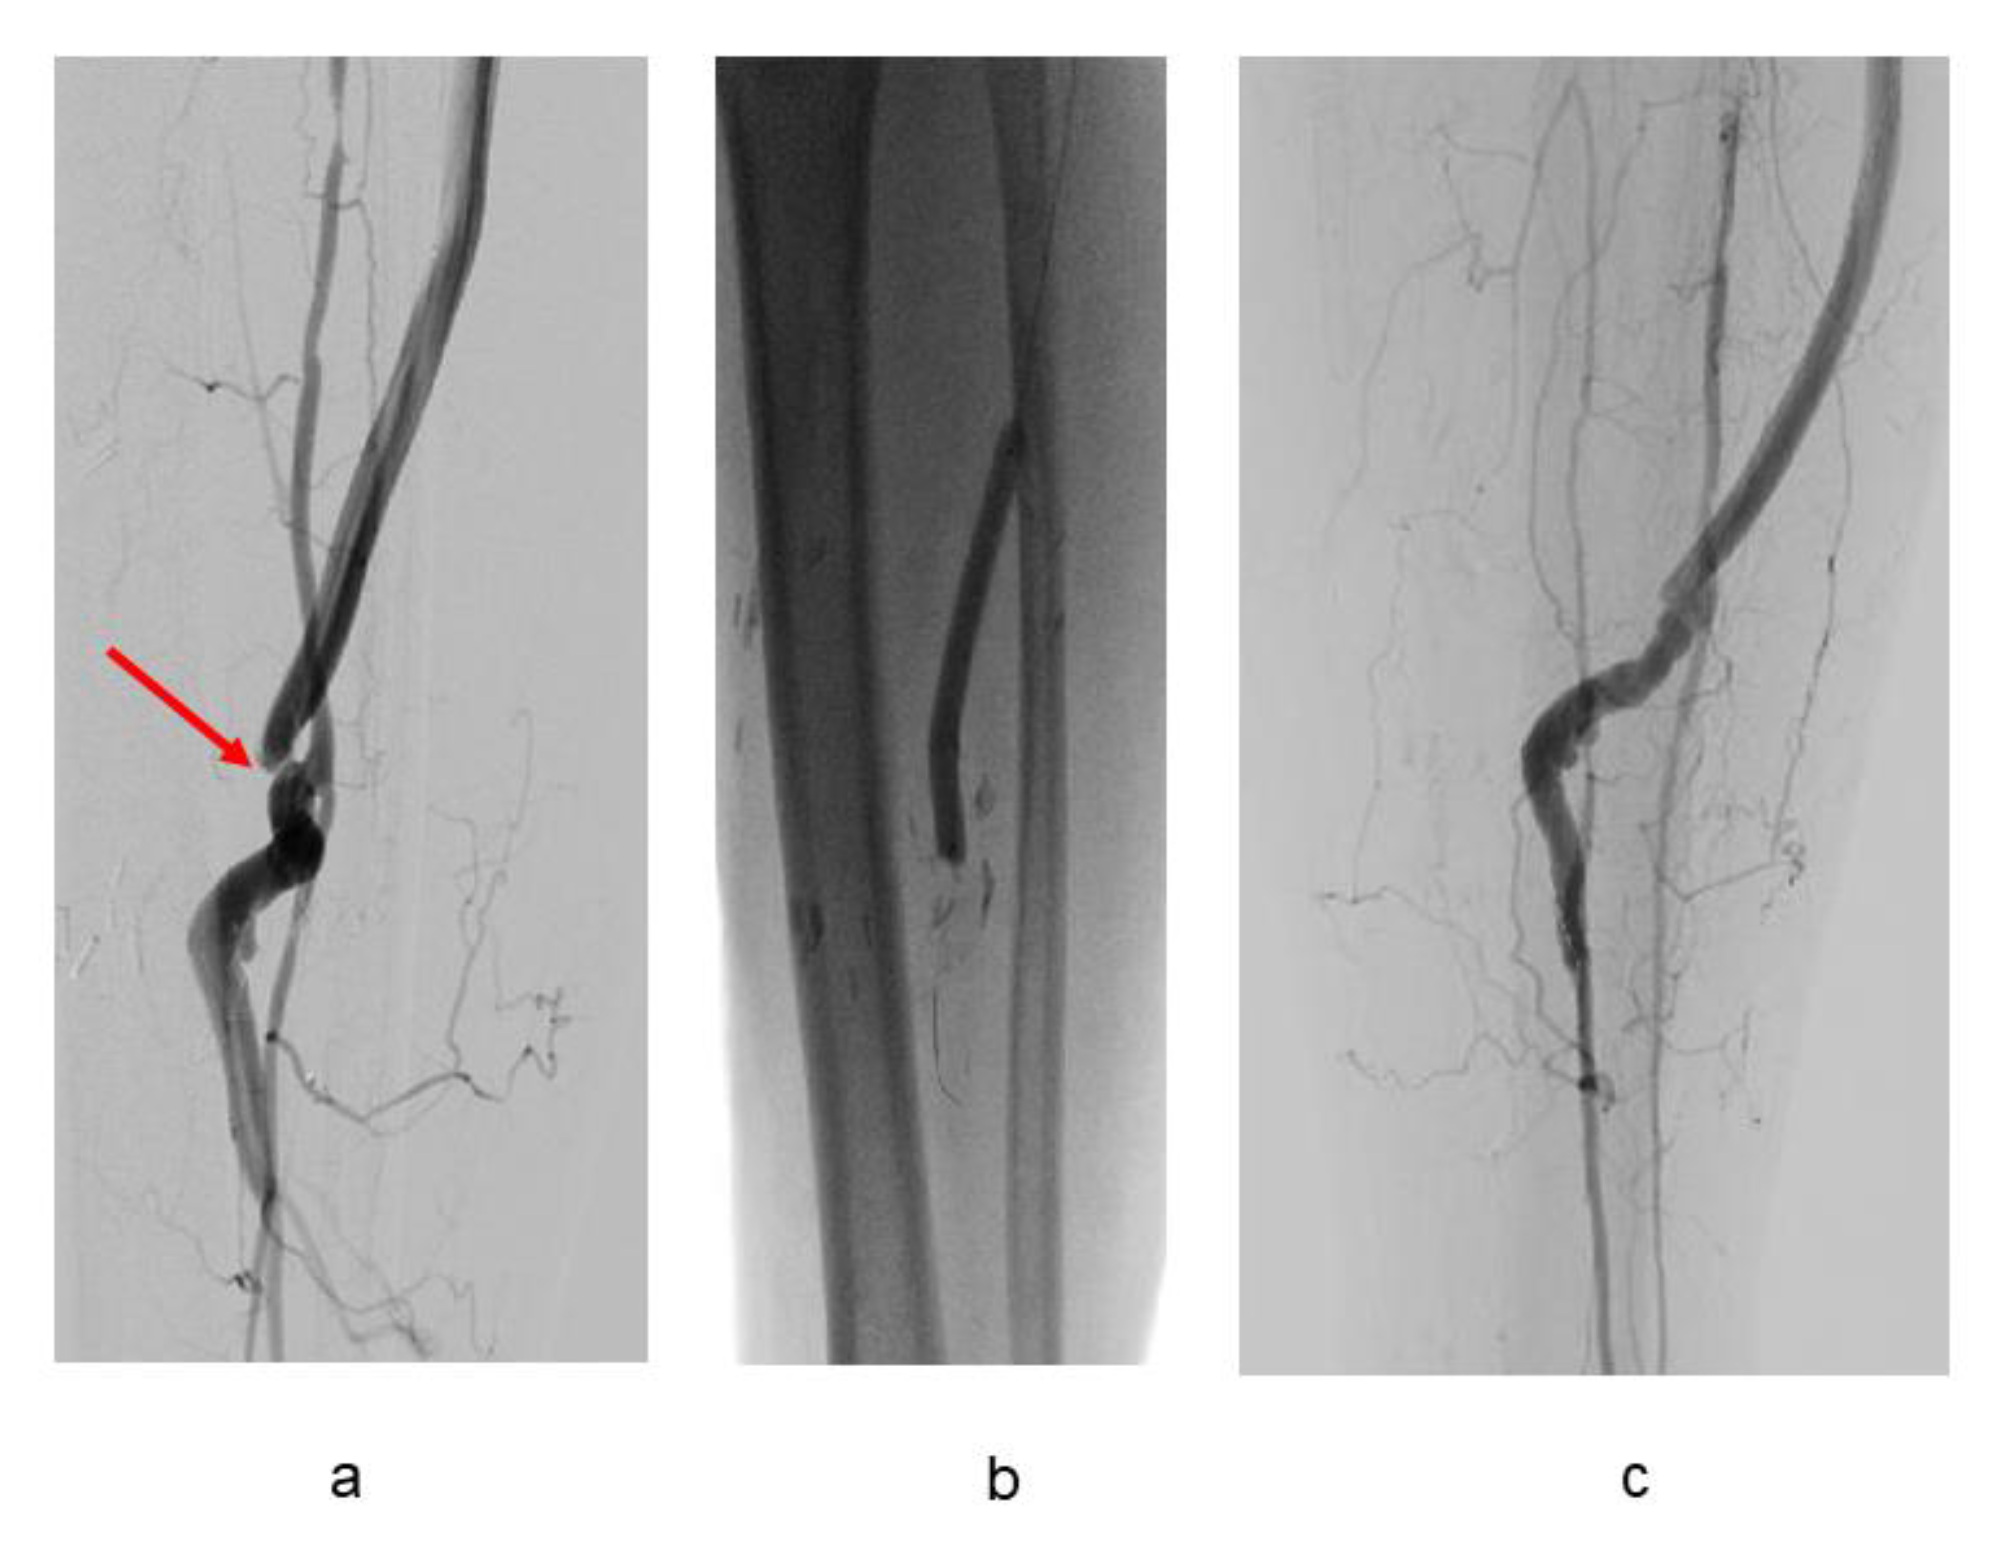

3.2. Bypass Configuration